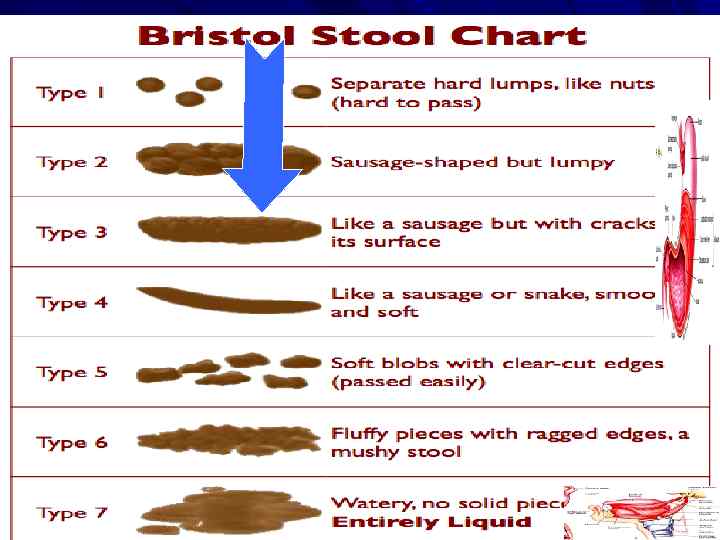

ДЕФЕКАЦИЯ КАЛ – гл. обр. в СИГМОВИДНОЙ КИШКЕ СЛАБЫЙ СФИНКТЕР и ОСТРЫЙ УГОЛ ПОПАДАНИЕ КАЛА в RECTUM → ПОЗЫВ КАЛ = 80 – 200 мл

ДЕФЕКАЦИЯ КАЛ – гл. обр. в СИГМОВИДНОЙ КИШКЕ СЛАБЫЙ СФИНКТЕР и ОСТРЫЙ УГОЛ ПОПАДАНИЕ КАЛА в RECTUM → ПОЗЫВ КАЛ = 80 – 200 мл